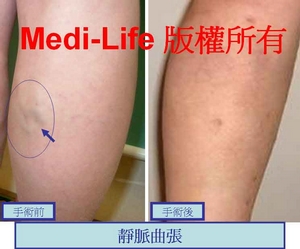

<案例二>

另一個案例: 手術後三週照片

另一個案例: 手術後三週照片